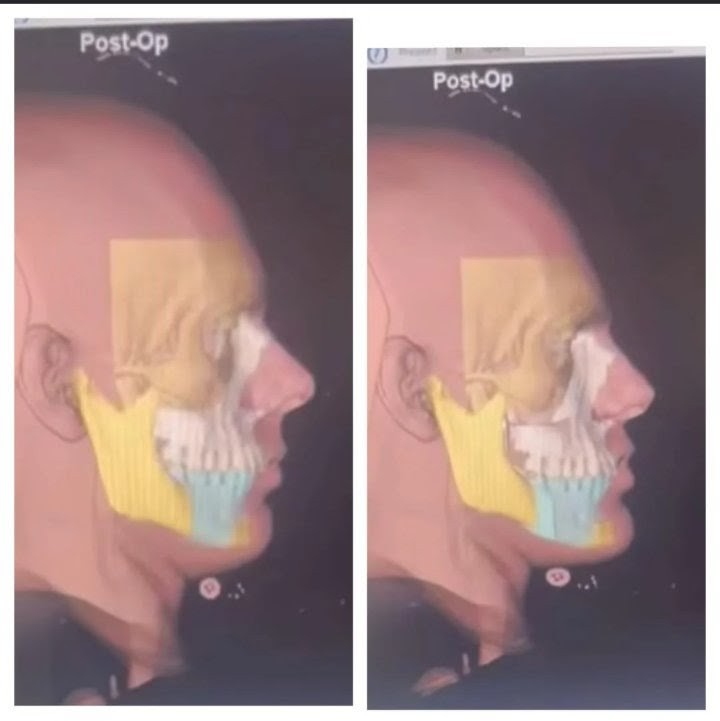

2. Bimax/Trimax

2. Bimax/Trimax